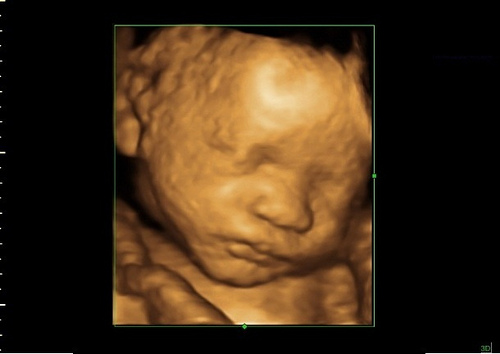

An ultrasound scan performed this week will show your baby moving his hands and feet and turning his head while also making different facial expressions. On a 3d ultrasound you can see your baby looking almost like how he is going to look at birth.